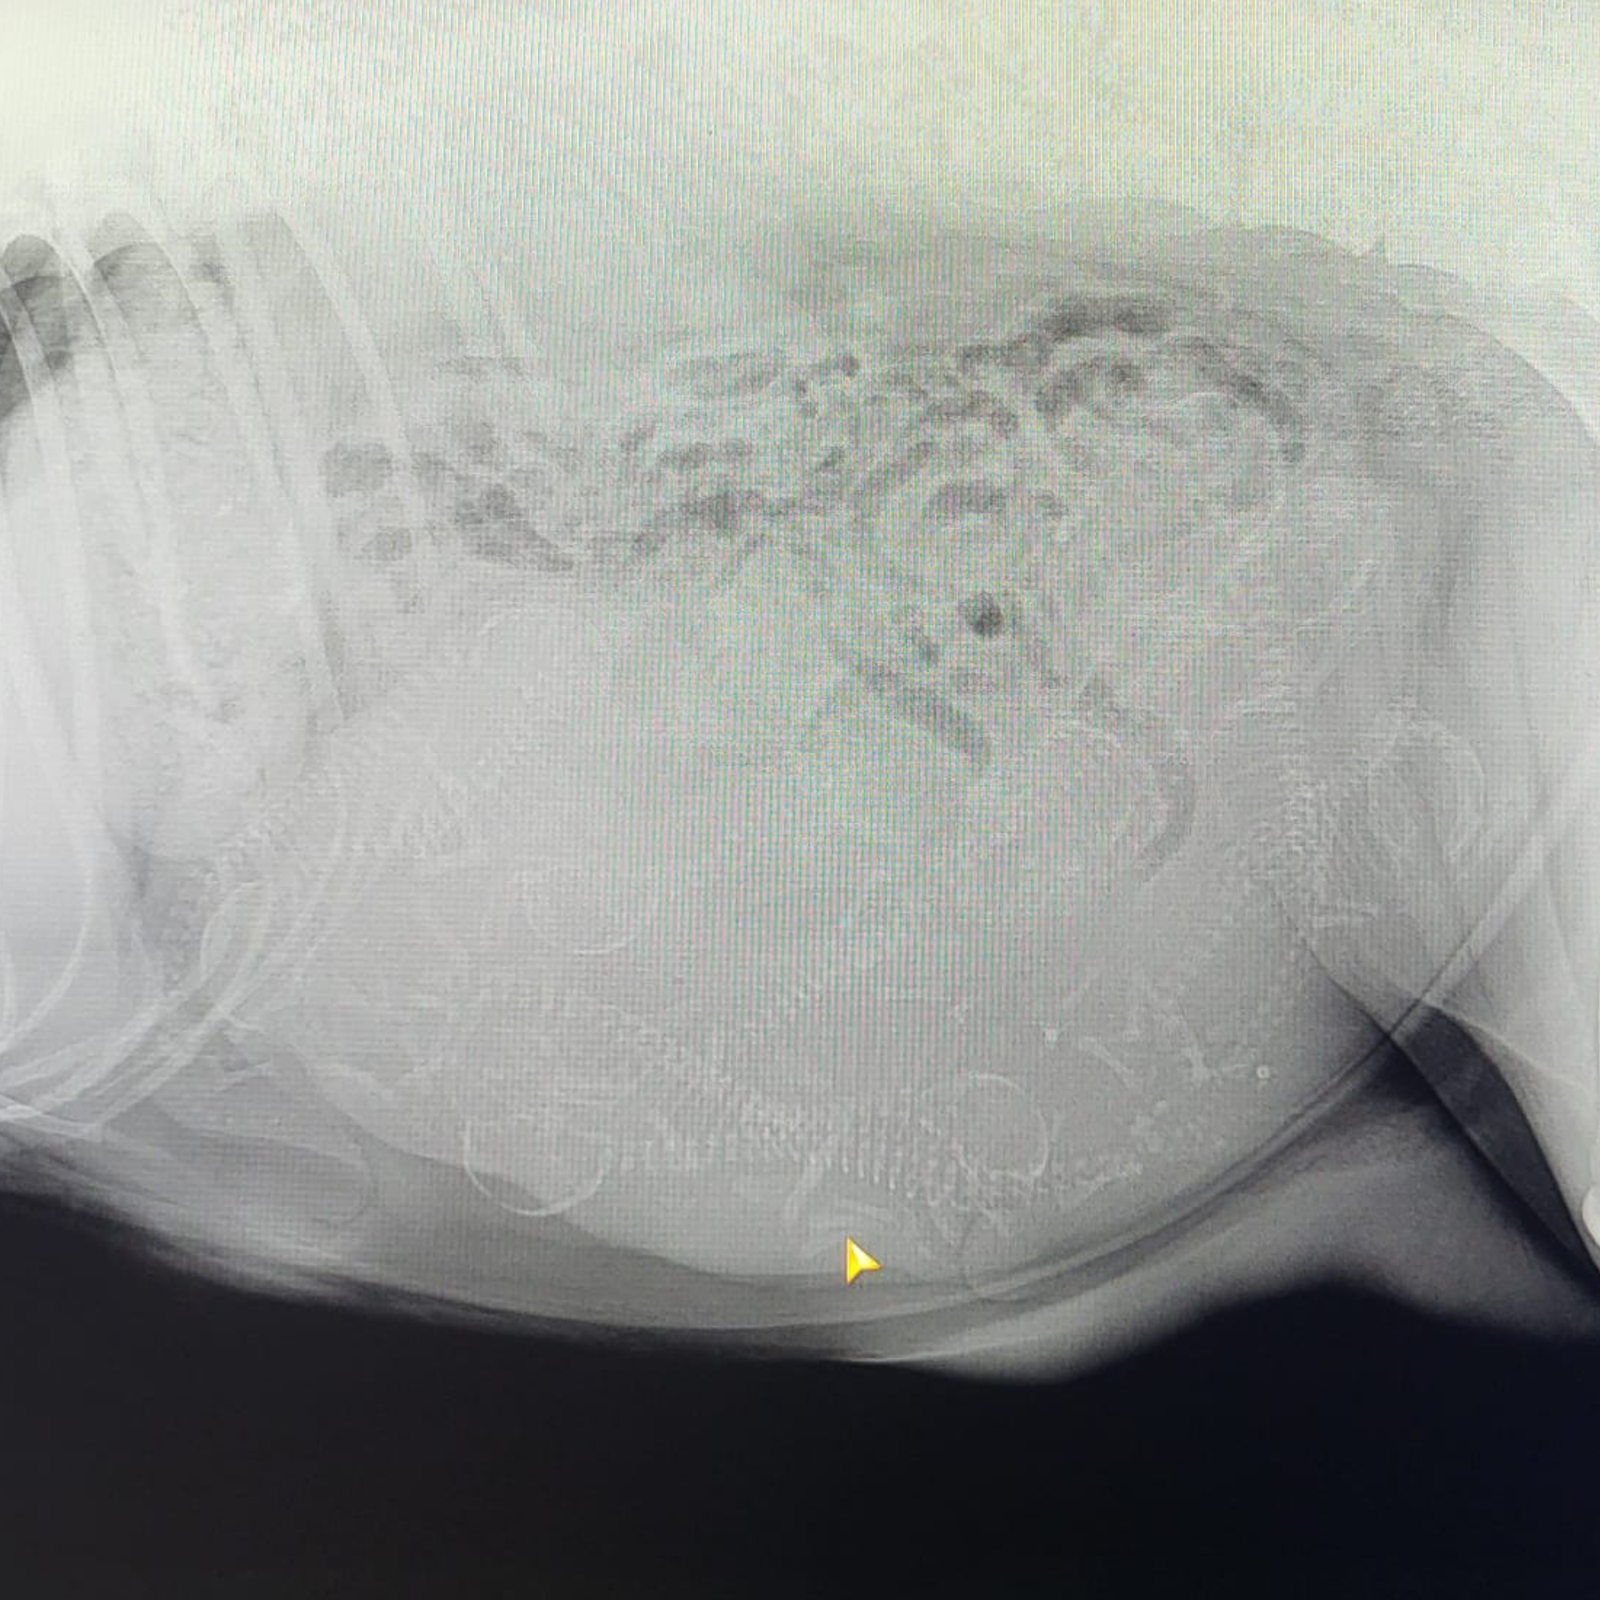

Echo en röntgenfoto!

Een röntgenfoto volgt binnenkort, zodat we een beter beeld krijgen van het aantal pups.